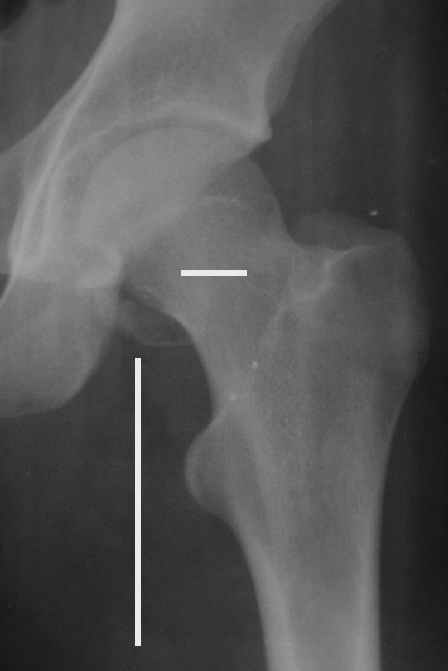

Уважаемые коллеги! Заканчивая обследование больного с переломо-вывихом бедра сделал ему обычные R-томограммы. Кажется удалось "поймать" и отломок и донорское место. Мои выводы - в скиаграмме. Считаю, что это передне-нижний фрагмент головки, образовавшийся вследствии отрывного перелома. На томограммах отломок обозначаю длинной стрелкой, а место откуда он оторвался - более короткой. Учитывая тот факт, что его размеры по КТ 25 х 15 мм считаю, что его фиксация на место необходима для профилактики артроза, что при 16-ти летнем возрасте пациента важно в плане максимального отодвигания эндопротезирования. Планирую оперировать его 24.05.05 г. Результаты представлю.

Прямой при поступлении

Несколько соображений к "картинкам". На прямом снимке и КТ-томограммах все типичные линии вертлужной впадины: крыша, передняя стенка, задняя стенка - сохранены. На КТ-сканах 6 и 7 появляется фрагментация головки. С учетом R-томограмм отломок расположен спереди-снизу, а не сзади-сверху от сустава, как написано в описании КТ.